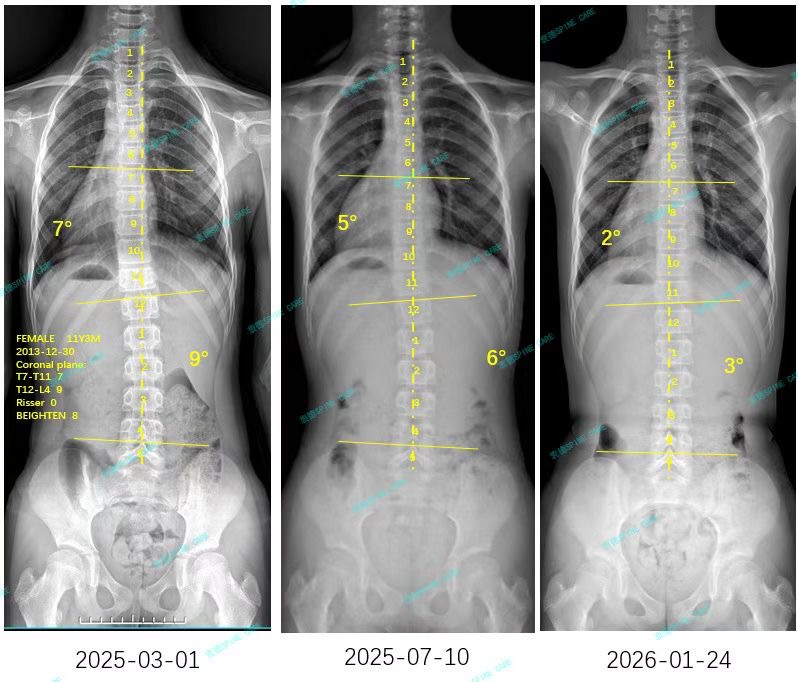

来自家长对衷德的评价(家家妈妈)

衷德脊柱,我们只关注侧弯保守治疗~

Zhongde Spine, bending no breaking ~